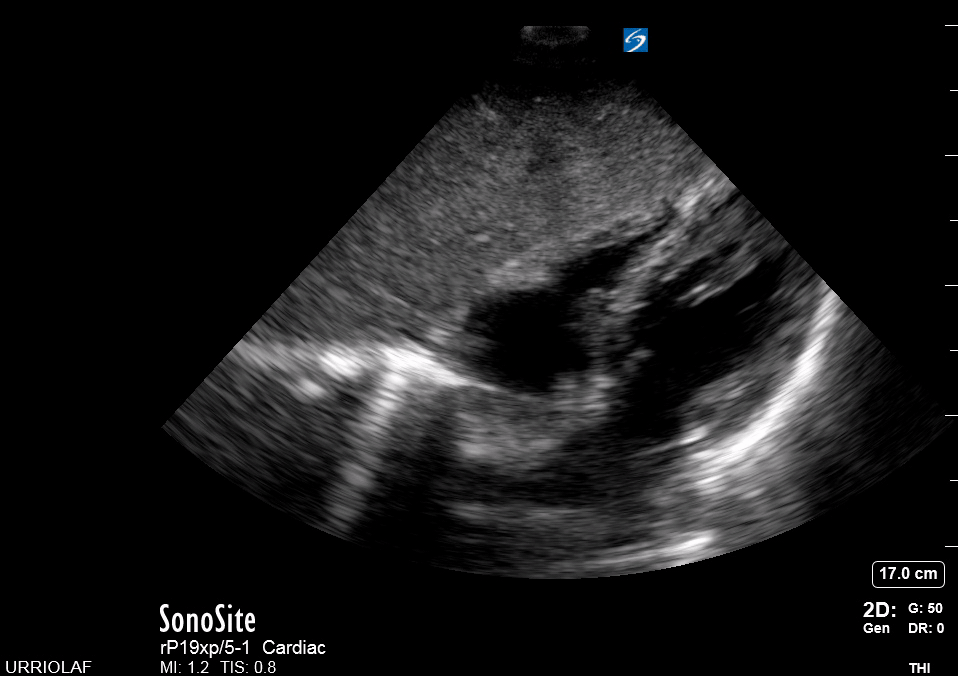

A correct PLAX view will align with the heart’s long axis, producing a sagittal cut. On the screen, from the top, we see the right ventricle, the interventricular septum, the left ventricle with its outflow tract, the aortic valve and aortic root, and the left atrium. It is essential to look for the descending aorta, which appears in a transversal cut deeper to the LV.

This is a versatile view and provides a considerable amount of information from different structures. It is useful to assess the left ventricle contractility, estimate the ejection fraction, and measure the aortic root size. It also gives insight into the chamber relationship (RV:AoRt:LA = 1:1:1) and differentiates pleural from pericardial effusion.